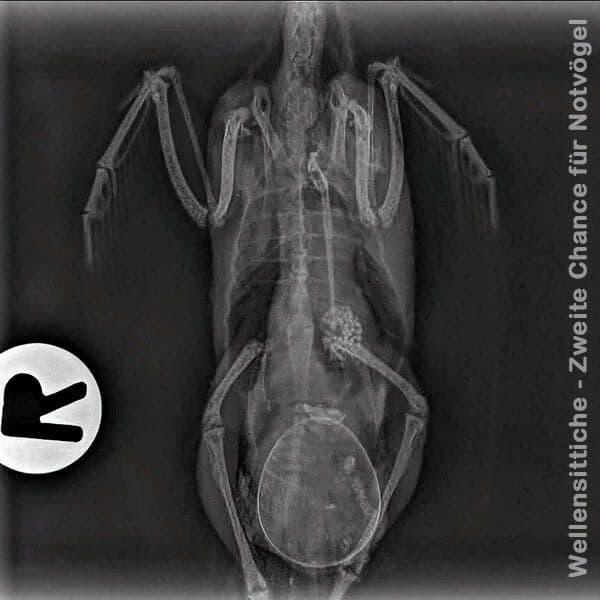

Lähmung durch ein verrutschtes Ei

Wenn durch einen Unfall, z.B. einen Sturz der Henne, das Ei verrutscht, kann dieses gegen die Wirbelsäule drücken und die dort verlaufenden Nervenstränge quetschen. Das kann zur Folge haben, dass die Henne ihre Beine nur noch schlecht oder gar nicht mehr bewegen kann.